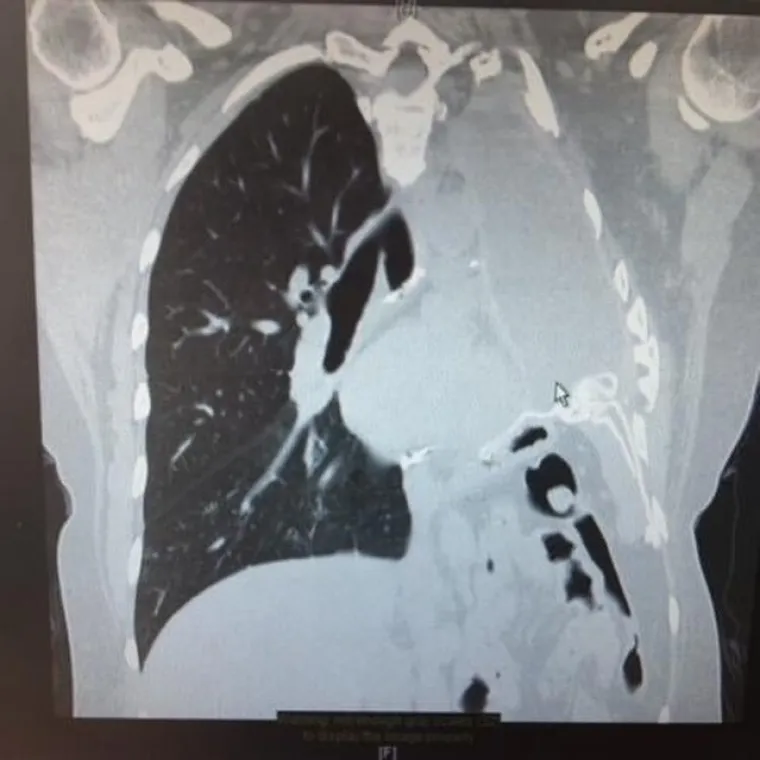

"Nakon nekoliko tjedana, znala sam da nešto ozbiljno nije u redu. Poslala sam sestri fotografiju na kojoj smo suprug, beba i ja spavali na kauču. Nazvala me u panici i rekla da na slici izgledam kao da sam mrtva te da odmah nazovem liječnika", prisjeća se. Uslijedio je niz medicinskih pretraga, a CT snimka otkrila je tumor blizu pluća. U roku od dva tjedna potvrđena je dijagnoza pleuralnog mezotelioma, agresivnog raka plućne maramice uzrokovanog izlaganjem azbestu.